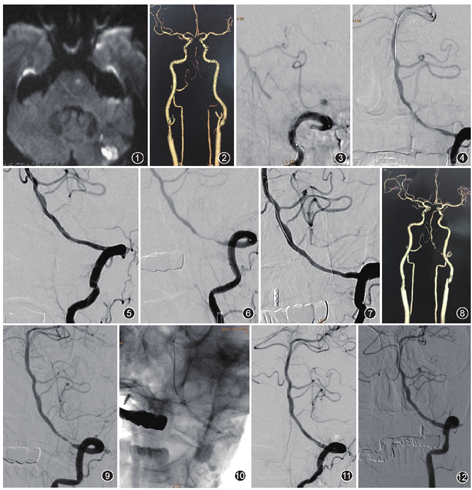

患者女,61岁。因"头晕伴行走不稳1年",于当地医院行MRI示左侧小脑半球、脑干梗死;CT血管成像(CT angiography,CTA)示右侧椎动脉纤细,V4段远端未见显影,左侧椎动脉V3段局部中度狭窄。予以药物对症治疗后,病情稳定好转出院。患者有糖尿病史10年,应用胰岛素治疗。出院后11个月复查,DWI示急性小脑及脑干梗死(图1),CTA显示左侧椎动脉进展为长节段闭塞(图2),急诊转我院。入院后DSA显示左侧椎动脉V3段长节段闭塞(图3),在全麻下实施左侧椎动脉闭塞开通术。穿刺右侧股动脉,置入6 F动脉鞘管,在泥鳅导丝配合下,将6 F ENVOY导引导管置于左侧椎动脉V2段,在SL10微导管配合下,将Traxcess14微导丝小心通过闭塞段。将SL10微导管跟进并跨过闭塞段后,造影确认其头端在基底动脉真管腔内,将Traxcess14微导丝沿微导管引入至左侧大脑后动脉P1段,微导丝尾端连接105 cm Traxcess Docking Wire后,交换撤出微导管系统,引入sprinter-legend(直径2 mm,长度12 mm)球囊至闭塞段,以8 atm(1 atm=101 325 Pa)压力充盈球囊扩张闭塞处,造影显示血管再通,残余狭窄40%(图4),随后更换sprinter-legend(直径2.5 mm,长度15.0 mm)球囊再次扩张狭窄处后,沿Traxcess14微导丝引入Wingspan(直径3 mm,长度20 mm)支架系统,准确定位后覆盖病变成功释放支架,造影显示支架展开良好,脑梗死溶栓血流分级(thrombolysis in cerebral infarction,TICI)3级(图5)。术后患者恢复良好,改良Rankin量表(modified Rankin Scale,MRS)评分1分。

术后7个月随访,DSA示Wingspan支架内严重狭窄(>95%,图6),先应用Fire Star(直径1.5 mm,长度15.0 mm)球囊扩张,血流明显改善后,更换mini trek(直径2.0 mm,长度15.0 mm)球囊再次扩张狭窄部位,扩张术后血管形态良好(图7),TICI 3级,继续药物治疗。

术后26个月(第2次球囊扩张成型后术后19个月)随访,CTA显示支架内再次发生狭窄(图8),继续药物对症治疗。

术后32个月随访,患者出现一过性复视症状,DSA显示Wingspan支架内重度狭窄(>95%,图9),决定应用药物涂层球囊(drug-coated balloon,DCB)再次扩张治疗。先以sprinter-legend(直径2 mm,长度15 mm)球囊预扩张病变后,应用DCB SeQuent Please(直径2.5 mm,长度20.0 mm,B.Braun Melsungen AG Melsungen,Germany)在支架内狭窄处,以8 atm压力扩张充盈球囊,持续接触60 s后(图10),撤除球囊系统,造影显示支架内狭窄解除(图11),TICI 3级。术后继续药物治疗。

DCB扩张后19个月随访,MRS 1分,复查DSA(图12)显示支架内无狭窄,血流通畅,TICI 3级。